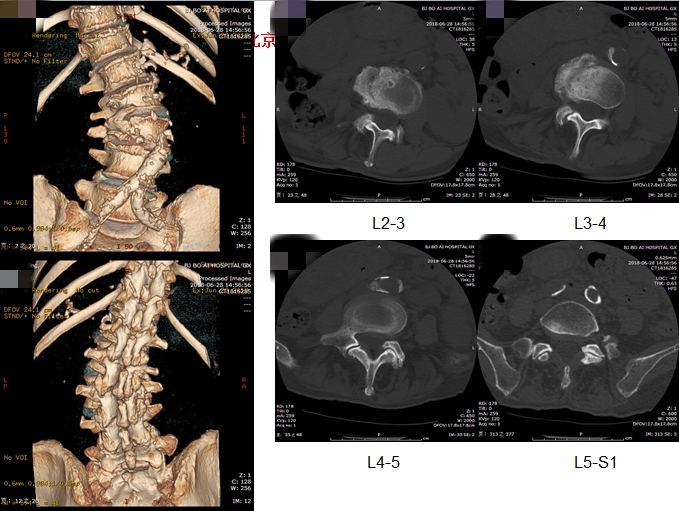

基本情况:女性,77岁,腰痛30年,加重一年,行走困难2月。身高158cm,体重190斤,就诊时轮椅推入病房。

影像检查:

洪毅教授:患者高龄,常年轻度慢性腰痛,本次加重1月余,无下肢神经功能损害,结合患者全长片、核磁体征表现,考虑患者疼痛加重原因为近期出现椎间关节损伤,需关注腰4-5,腰5-骶1节段。腰4-5小关节增生明显,椎间盘高度尚可,不能排除小关节骨关节病。腰5-骶1有ModicII期表现,可能为间盘源性疼痛来源,可进行诊断性封闭治疗。

孙常太教授:患者影像退变性骨关节病表现重,无椎管狭窄。虽有侧凸,但腰2-3,腰3-4侧弯节段可见明显的骨赘形成,稳定性强,腰5-骶1节段椎间盘高度已塌陷,亦较稳定,仅腰4-5节段仍有一定活动度,这就形成腰4-5节段的应力集中,体格检查压痛点与小关节位置亦吻合,需考虑重点关注此节段。

谭荣教授:同意孙教授意见,腰4-5节段动力位显示仍有一定活动度,同时腰4有I°滑脱,证明节段不稳定。病史中患者起身、刚下地时症状重亦支持节段不稳的表现。核磁腰4-5轴位可见明显的小关节病表现,Weishaup分级IV期,亦支持相关诊断。